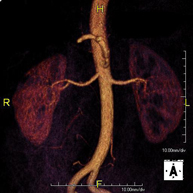

- Angio-RM Aorta abdominal

Prueba diagnóstica no invasiva que consiste en el estudio de la arteria aorta abdominal, obteniendo imágenes de alta definición anatómica mediante el empleo de un campo electromagnético y ondas de radio (con un emisor y un receptor). Es indispensable el uso de contraste paramagnético (Gadolinio). Sin embargo, no utiliza radiación ionizante. La calidad de las imágenes permite realizar reconstrucciones en 2D y 3D. Está indicado en aquellos pacientes con enfermedad vascular (aterosclerosis), estudio de aneurismas, en estudios pre-quirúrgicos de lesiones adyacentes a la aorta abdominal como "mapa" vascular, etc.

- Angio RM Aorta-ilíaca

Prueba diagnóstica no invasiva que consiste en el estudio de la arteria aorta abdominal de las arterias ilíacas, obteniendo imágenes de alta definición anatómica mediante el empleo de un campo electromagnético y ondas de radio (con un emisor y un receptor). Es indispensable el uso de contraste paramagnético (Gadolinio). Sin embargo, no utiliza radiación ionizante. La calidad de las imágenes permite realizar reconstrucciones en 2D y 3D. Esta prueba está especialmente indicada como estudio pre-quirúrgico (mapa vascular) antes de intervenciones percutáneas o quirúrgicas de aorta abdominal y arterias ilíacas, estudio complementario en pacientes con isquemia de miembros inferiores, etc.